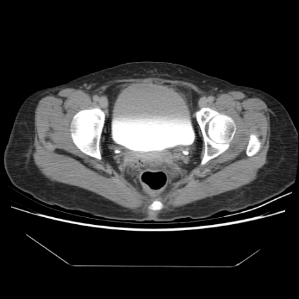

One hundred consecutive IC patients were investigated by symptom score, urodynamic study, cystoscopic hydrodistention, and bladder CT study. The BWT is divided into smooth (n=49), focal thickness (n=15), and diffuse thickness (n=36) subtypes, which are demonstrated in Figure 1.

Figure 1. Subtypes of BWT demostrated on CT